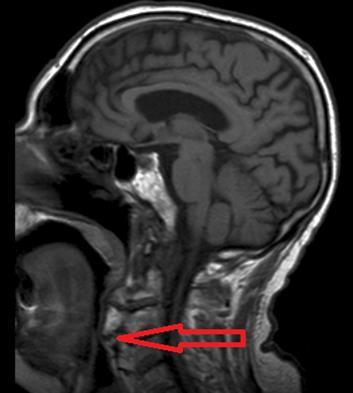

Brain and cervical MRI were performed to exclude recent brain ischemic lesions and to investigate the spinal chord involvement in relation to the known severe osteophytosis. The brain MRI showed only signs of chronic vasculopathy and no images related to acute events. The neck MRI revealed no medullary compression or signal alterations; osteophytes originating from C1 to C7 were described and had a compressive and displacing effect on the upper aero-digestive ways and laryngeal post-cricoid area. Osteophytes were forming bony bridges in the anterior prevertebral space from C3 to C7.

Figure 1.Osteophytes-induced upper airways obstruction

Osteophytes-induced upper airways obstruction